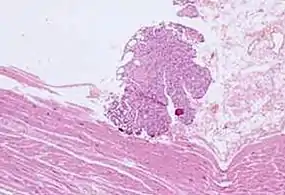

Cardiac muscle (bottom) with contamination from thyroid tissue (center) Crush artifact from compression by forceps on the tissue sample

Crush artifact from compression by forceps on the tissue sample Folding artifacts (white arrows) and a crush artifact (black arrow, with cytoplasmic hypereosinophilia and nuclear pleomorphism) from a needle.

Folding artifacts (white arrows) and a crush artifact (black arrow, with cytoplasmic hypereosinophilia and nuclear pleomorphism) from a needle.